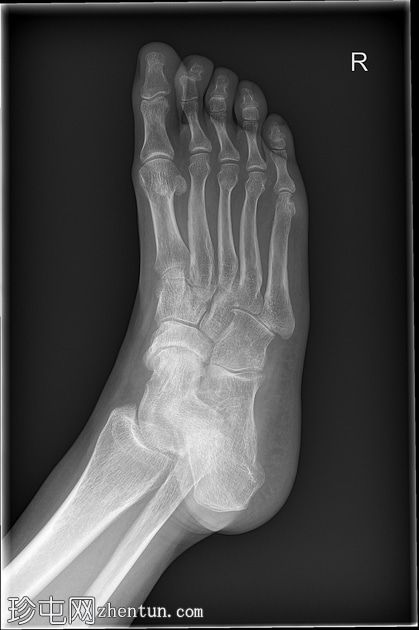

X线片

多发性

骨质疏松伴皮质变薄

左侧和右侧第五跖骨头关节旁骨侵蚀

边界不清